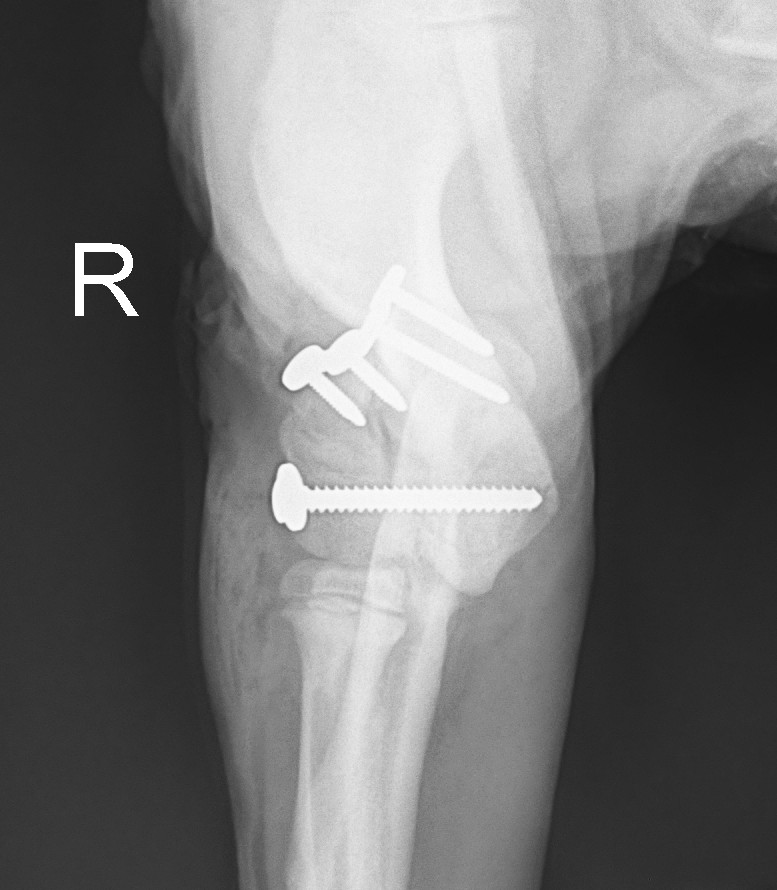

Otto came to us from another practice as we now offer surgical referrals to pets whose own practice can’t fix them for whatever reason. Simon put his elbow back together and put a screw across the elbow to hold it in position, with a small stainless-steel plate and screws across the broken ridge as well.

Otto’s owner now has the hard part – keeping Otto in a cage for 4 weeks :-0

He’s been a very good boy so far, so fingers crossed. It’s important that he rests strictly so that the bones can heal – if they heal in the position that they were when he came off the operating table, he will make a full recovery.